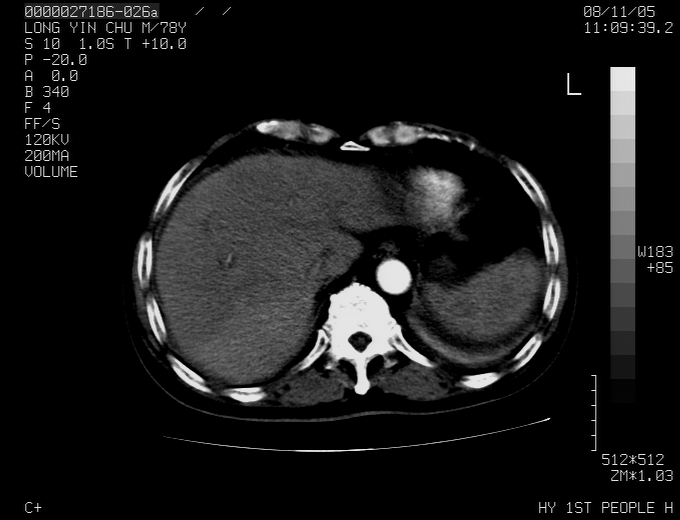

标题: CT16532:M78Y,肝脏病变,请会诊 [打印本页]

标题: CT16532:M78Y,肝脏病变,请会诊

腹胀,腹痛就诊,男性,78岁,外院b超未见异常。

肝ca,脾肾转移

支持脾肾转移瘤,双侧胸腔积液。

考虑弥漫性肝癌并脾及双肾转移.双侧胸水.

图片质量欠佳:多考虑:左侧肾癌。脾脏转移!胸膜转移!

考虑弥漫性肝癌并脾及双肾转移.双侧胸水.  支持

肝脾肾转移瘤可能性大,左肾不除外梗塞,双侧胸水

考虑弥漫性肝癌并脾及双肾转移,双侧胸水。

考虑肝癌并双肾及脾脏转移;双侧胸腔积液。